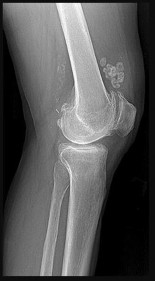

Figures 22a and 22b are the anteroposterior knee radiograph and an axial T2-weighted MR image of an 11-year-old boy who experienced knee pain following soccer practice. What is the best approach for biopsy?

The biopsy should cross only 1 compartment if possible and proceed as directly as possible to the tumor. The lateral parapatellar and medial parapatellar approaches cross the knee joint, potentially visualizing tumor into the knee. A direct anterior approach will contaminate an extensive portion of the quadriceps muscle and potentially complicate limb salvage. Biopsy should be performed at the institution at which definitive resection is planned.